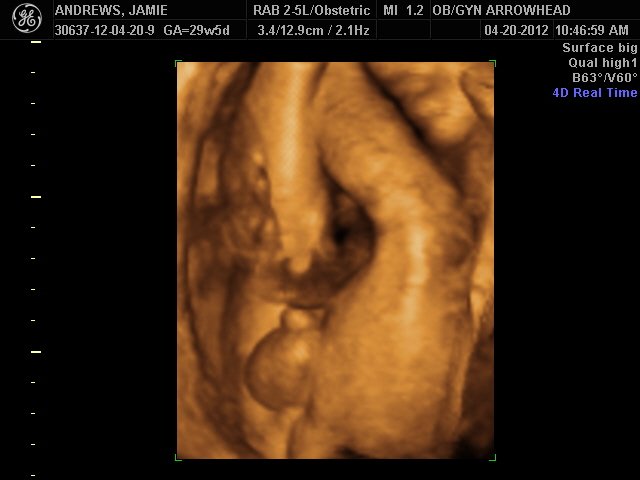

We offer complimentary 3D/4D Ultrasounds to all our OB patients around 30 weeks! The following photos are some examples of our work, shown with permission from our patients.